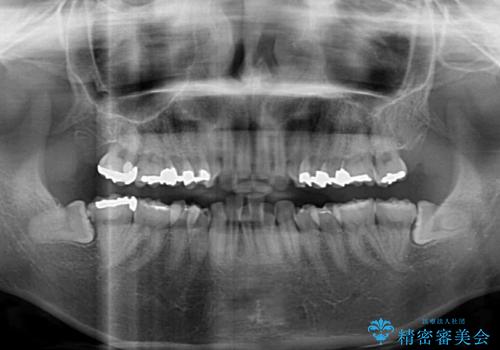

- 上下の出っ歯を気にして来院された患者様です。

口元を積極的に引っ込めるために、上下左右の第一小臼歯を4本抜歯することとしました。

元々ディープバイトのため、スペースを閉じている期間に上下前歯が接触してしまい、治療期間が想定よりも伸びてしまいました。